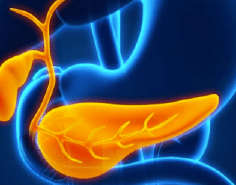

Vesícula Biliar

La cirugía de la vesícula biliar, llamada Colecistectomía Laparoscópica, es el procedimiento por el cual se lleva a cabo la extirpación de la vesícula. Este tipo de cirugía está indicada cuando la vesícula biliar contiene litos o piedras en su interior causando un proceso inflamatorio agudo o crónico llamado Colecistitis Litiásica. Los síntomas dependerán si se presenta el cuadro clínico de manera crónica con dolor abdominal de larga evolución en región subcostal derecha, nausea, vómito o si los síntomas se presentan de manera súbita con dolor abdominal de gran intensidad requiriendo de manejo quirúrgico de urgencia.

La cirugía se realiza mediante laparoscopía a través de 3 pequeñas incisiones de 5 y 10 mm, extrayéndose la vesícula por una de estas heridas, lo cual permite excelentes resultados estéticos, una pronta recuperación con mínimo dolor y una rápida reintegración a sus actividades. A pesar de que es un padecimiento frecuente, se requiere amplia experiencia para evitar complicaciones o lesiones desencadenadas durante la cirugía, es por ello que ofrecemos una atención de alta calidad, con el mejor equipo médico y técnico para poder resolver esta patología con la menor probabilidad de riesgos o complicaciones y con una recuperación prácticamente inmediata.